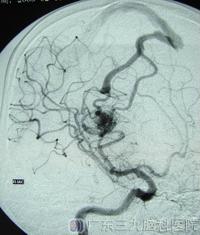

术前DSA检查及MRA检查见畸形血管团。